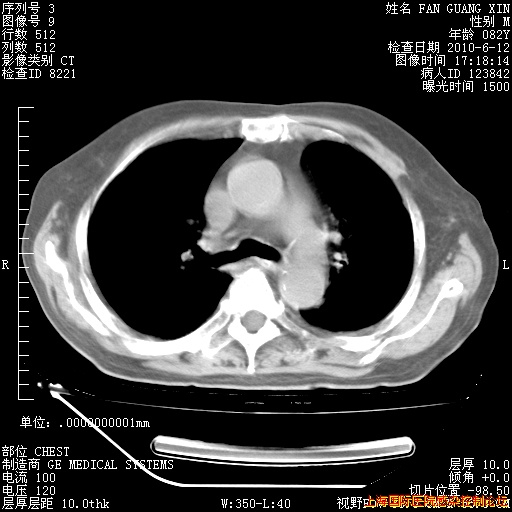

补发6月12日肺部CT肺窗

6月12日肺窗